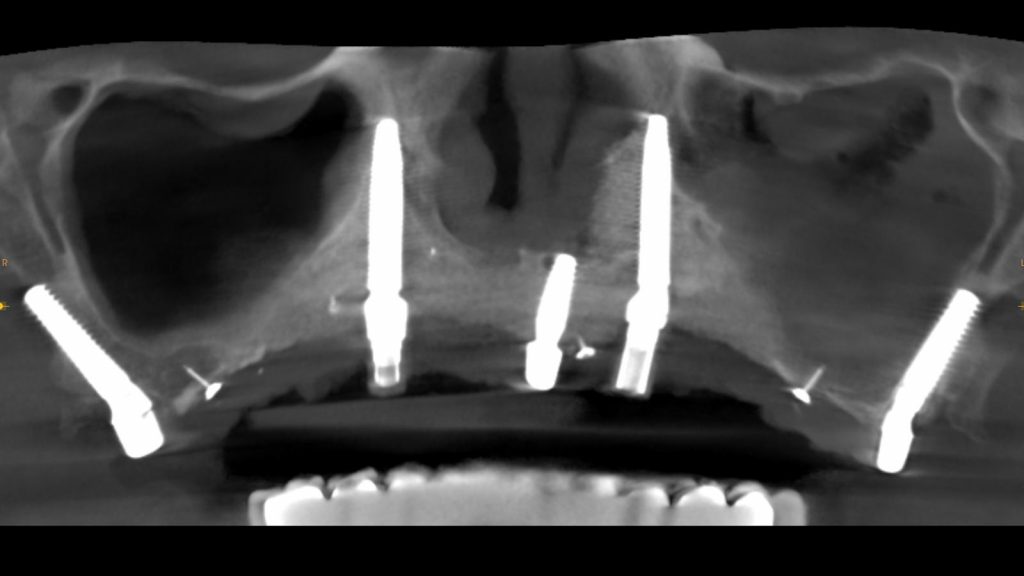

Implantes transnasales fotos y resultados

Te mostramos algunos casos reales tratados en nuestra clínica con implantes transnasales.